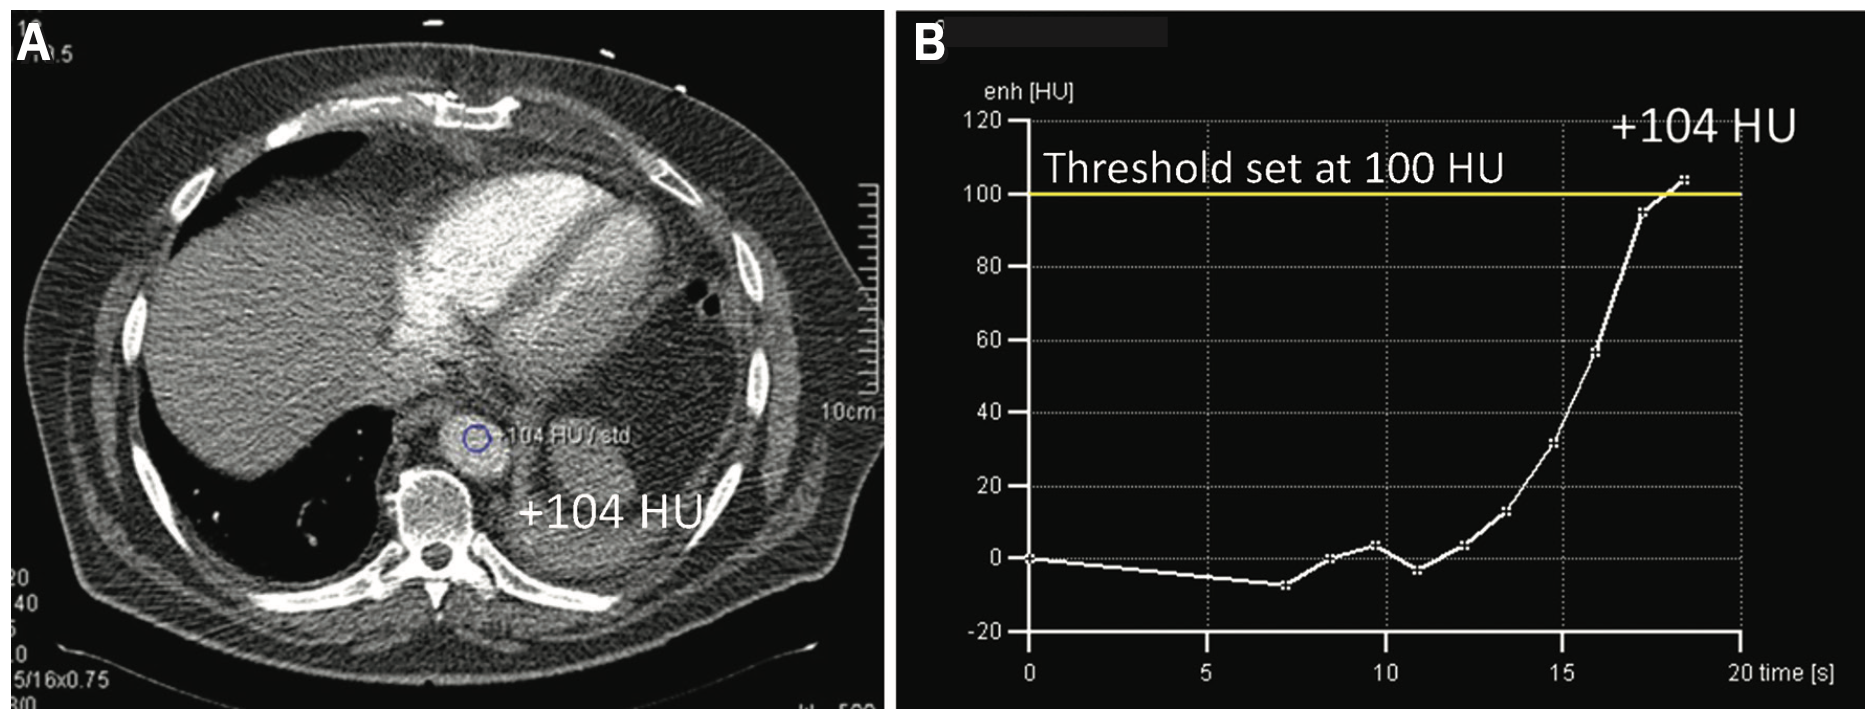

CCTA uses approximately 75 mLs of IV contrast with normal saline to image the coronary arteries and adjacent structures. An antecubital IV of 20 gauge or larger is recommended to deliver the bolus. The use of a bolus tracking technique is utilized to optimize peak enhancement of the IV contrast to the vascular target structure. An automatic software enables the triggering acquisition of the CT scan at the optimal phase of the contrast enhancement, creating improved image quality and higher reliability, and added confidence for the CT technologist. Acquisition is accomplished while the CT scan tracks the IV contrast within the blood at a predefined density, or threshold (100 HU), via the area’s region of interest (Figure 3). Once the threshold is reached, the scan is acquired.